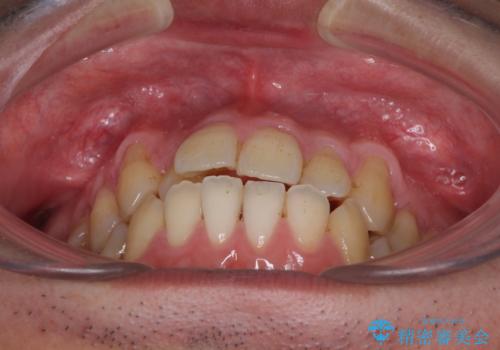

- 上下の前歯の反対咬合を気にして来院された患者様です。

インビザラインを用い、下顎はIPR(歯と歯の間を削る)と歯列全体を後方に移動させ、上顎は前歯を持ち上げることで、反対咬合を改善していくこととしました。

インビザラインによる反対咬合の改善は、上の歯が下の歯を乗り越えていく期間に咬み合わせが非常に不安定となり、治療が長期化することがあります。

また、ワイヤー矯正と異なり歯軸改善の強い力を前歯にかけるため、反対咬合で裏側にある歯の歯肉が退縮しやすくなります。